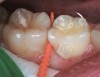

The authors' protocol for insertion of SDF-coated soft dental picks involves isolating the teeth with cotton rolls or other means, flossing the interproximal site to clear food debris and dental plaque, and then inserting a SDF-coated pick (Figure 1 and Figure 2) to saturate the contacting surfaces of the teeth with the fluid. This treatment is painless and requires no anesthetic. The pick should remain in place for at least 60 seconds and can be gently pulled in and out to agitate the fluid for enhanced surface coverage by capillary action. Additional SDF can be wiped on, using a small applicator, above the contact and in the buccal and lingual sluiceways. Excess fluid and any blood elicited may be blotted with a cotton swab. An additional 60-second insertion may be applied in the same way if there is radiographic evidence of a deeper decalcification or caries lesion. With the pick still in place, 5% (or 2.5%) fluoride varnish is painted over the treatment area, and the pick is then withdrawn.

Fig 3. Three thin soft dental picks were used simultaneously for SDF proximal surface saturations in a teenaged patient (Fig 3). After 60 seconds, the treated regions were covered with 5% fluoride varnish (Fig 4). A comparison can be seen of pre-SDF-treatment bitewing films (Fig 5) and 8-month post-SDF bitewing films (Fig 6) for the patient shown in Fig 3 and Fig 4. Radiolucencies were similar or improved, except for contact of maxillary first and second molars.

Figure 3